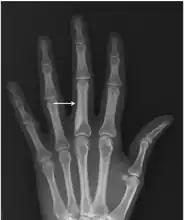

It is a genetic disorder associated with LEMD3.[6][7] It is inherited in an autosomal dominant manner.[2] In a very few, X-rays may show several areas of compact bone.[1] Conditions that may appear similar include tuberous sclerosis, pseudoxanthoma elasticum, neurofibroma, and lipoma, among others.[1]

• X-ray